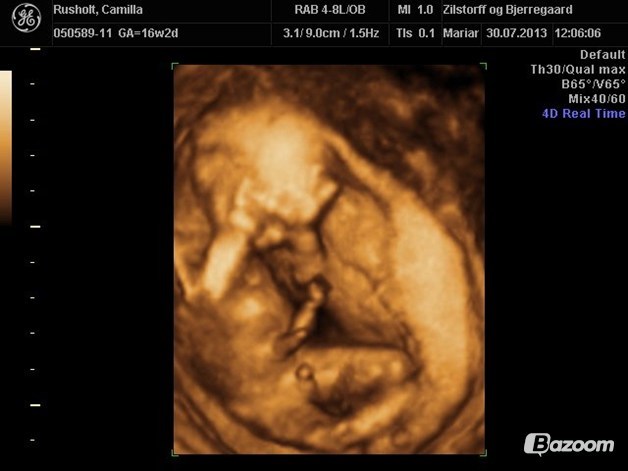

Kløver

Vi fik 3D med min søn uge 16 og kønsscanning istedet med min datter, og begge fået 3D efter md

Deler lige 2 billeder fra min søns 3D uge 16

Vedhæftede fotos (klik for at se i fuld størrelse)